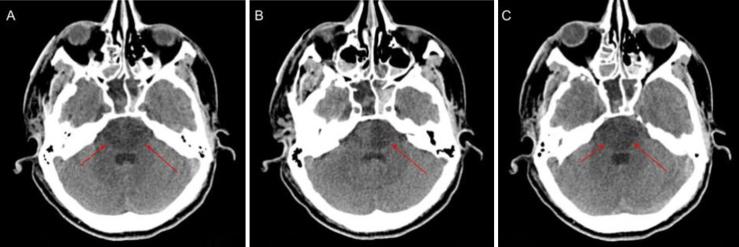

The reported case is of a 37-year-old male who presented following a 20-foot fall. CT angiography revealed a longitudinal fracture of the posterior wall of the right sphenoid sinus with basilar artery incarceration. CT of the head revealed pontine infarct with extension to the midbrain, indicating concern for severe shear injury and incarcerated basilar artery. The patient was transitioned to comfort care after discussion with his family.

报告的病例为一名37岁男性,因从20英尺高处坠落就诊。CT血管造影显示右蝶窦后壁纵行骨折伴基底动脉嵌顿。头颅CT显示脑桥梗死并延伸至中脑,提示存在严重剪切伤及基底动脉嵌顿。与患者家属讨论后,患者接受了舒适护理。